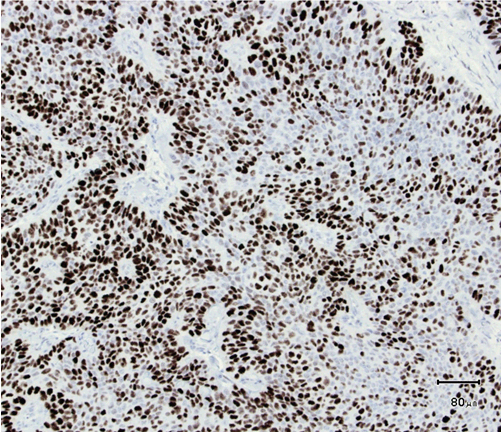

A 61-year-old male was presented to his dermatologist with a solitary nodular dermal lesion on his lower back (1.5x2 cm). He was otherwise well and was taking no medication. A biopsy demonstrated squamous cell carcinoma (SCC), and the patient was referred to our service for complete local excision. On follow-up, a month later, the patient presented with hemoptysis, hip-, and abdominal pain. Magnetic resonance imaging (MRI) scan confirmed the presence of lung, liver, and bone multiple metastases. As planned, a complete local excision with a 7.5 mm margin was performed. Histology confirmed the diagnosis of SCC. Furthermore, the patient had developed another solitary dermal lesion localized to the chin. This lesion was not present only a month prior during the visit to the dermatologist. A biopsy from this lesion also demonstrated SCC. The specimens from the back and chin were later studied with immunohistochemistry. The morphology suggested SC, with the tumor showing a solid arrangement of cells with nuclear pleomorphism, atypical mitosis, basophilic and vacuolated cytoplasm (Figure 1) and (Figure 2). In addition, immunohistochemistry showed tumor positive for epithelial marker Ber-EP4, pancytokeratin (Kl1) and epithelial membrane antigen (EMA) (Figure 3). Reactivity for p53 and proliferating cell nuclear antigen (Ki67) was high, showing 80–90% hot spots labeling of the tumor cells (Figure 4) and (Figure 5). Immunoreactivity levels of cancer protein p53 and Ki67 above 10 and 25% indicated a poor prognosis (Figure 6). It was then concluded that the correct diagnosis of both tumors was in fact SC and not SCC.

Figure 5: Hot spots for Ki67 (H&E stain, x100).